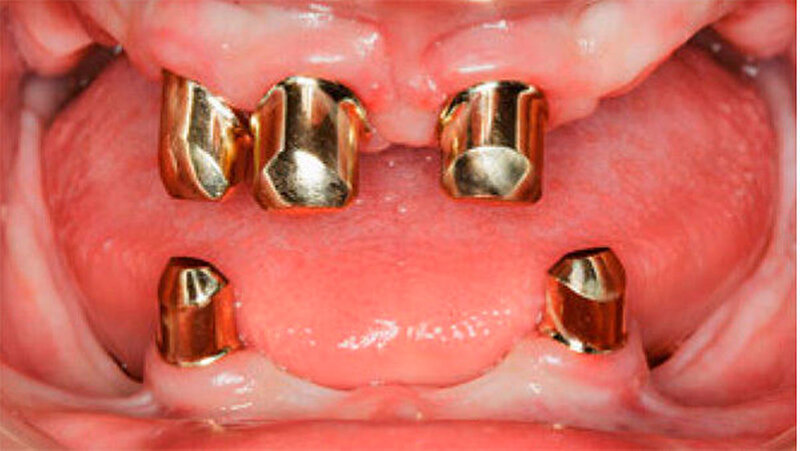

Der bei Behandlungsbeginn 14-jährige Patient war mit einer neun beziehungsweise fünfjährigen Prothese im Unter- beziehungsweise Oberkiefer versorgt (Abb. 2 und 3). Die angelegten Zapfenzähne 12, 11 und 21 waren bereits mehrfach konservierend restauriert und wiesen diverse Stellen mit Sekundärkaries auf. Die Kronenränder der Zähne 33 und 43 waren deutlich sondierbar. Der Kieferkamm im Unterkiefer war aufgrund der fehlenden Zahnanlagen sehr schmal (Abb. 4 bis 6). Die Panoramaschichtaufnahme zeigte das reduzierte vertikale Knochenangebot (Abb. 7). Da die Vitalerhaltung der wenigen Restzähne aufgrund des jungen Alters des Patienten unbedingt anzustreben war, wurde als Behandlungsziel im Ober- und Unterkiefer eine Versorgung mit Hybridprothesen, retiniert auf Teleskopkronen, festgelegt.

Nach Einprobe der Aufstellung der Prothesenzähne in Wachs wurden die Primärteile aus Gold und deren Galvano-Sekundärteile hergestellt. Letztere wurden in die fertige Prothese eingeklebt (Abb. 12 und 13). Auf eine gegossene Gerüstverstärkung wurde aufgrund des ausreichenden Platzangebots und der relativ geringen Kaufkräfte bei dieser, als Übergangsprothese geplanten Arbeit, aus Kostengründen verzichtet. Zur Erhöhung der Bruchzähigkeit erfolgte die Prothesenherstellung mit dem IvoBase® System (IvoBase® Injector, IvoBase® High Impact). Eine zusätzliche Glasfaserverstärkung zur Frakturprophylaxe wurde in den Prothesenkunststoff eingearbeitet.